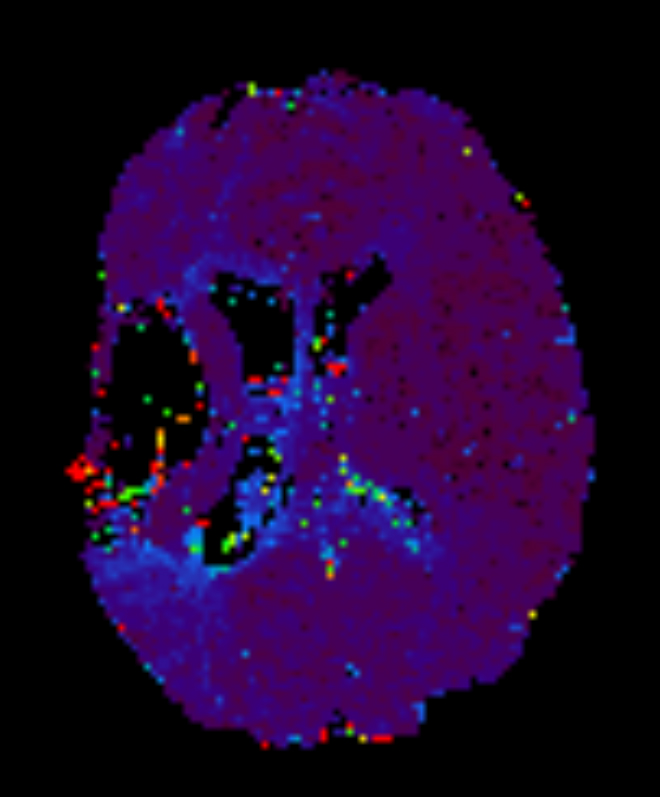

Axial 3D APT

Axial T2* Perfusion - rCBF

Axial T2* Perfusion - TTP

Axial T2* Perfusion - TO